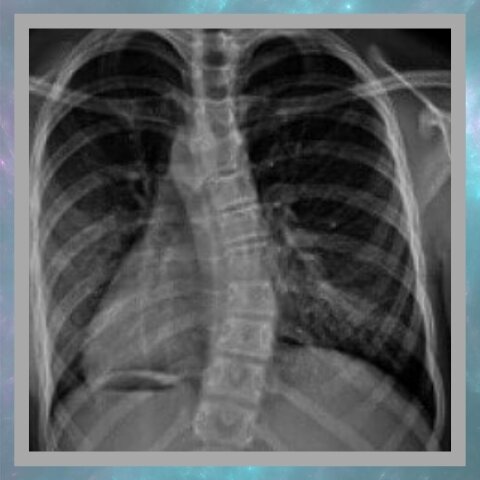

Что еще можно оценить сразу? Деформации позвоночника - усиление изгиба в грудном отделе позвоночника и/или сглаженность в поясничном отделе. В старческом возрасте это говорит в пользу остеопороза, в молодом - анкилозирующего спондилита.